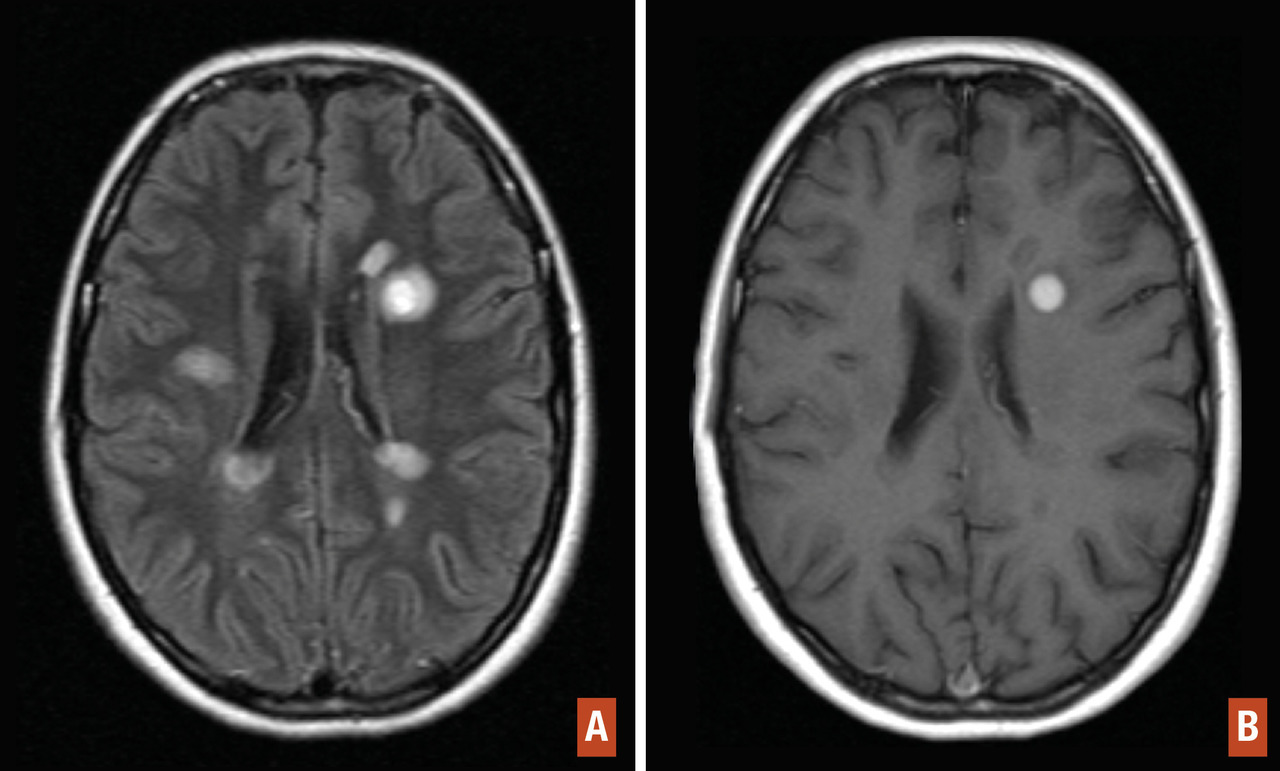

Des critères diagnostiques de la sclérose en plaques ont été établis (tableau 1). Ces critères peuvent permettre le diagnostic de sclérose en plaques dès la première poussée à condition que les critères de dissémination spatiale et temporelle soient remplis. La dissémination spatiale est définie par la présence d’au moins une lésion T2 dans 2 des 4 localisations considérées comme caracté­ristiques de la sclérose en plaques : juxtacorticale, périventriculaire, infratentorielle, au niveau de la moelle épinière (tableau 2 ; fig. 7).

La dissémination temporelle est prouvée par l’apparition d’une lésion en T2 quel que soit le délai par rapport à l’IRM initiale ou par la présence sur l’IRM initiale à la fois de lésions se rehaussant par le gadolinium (signant une lésion récente) et de lésions ne se rehaussant pas (tableau 3). Cette deuxième possibilité évite d’attendre la deuxième IRM pour poser le diagnostic de sclérose en plaques chez certains patients avec un syndrome clinique isolé (ou premier événement démyélinisant). La réalisation d’une seconde IRM est nécessaire pour confirmer une dissémination temporelle chez les patients ne remplissant pas ce critère sur l’IRM initiale. L’alternative permettant de suppléer le critère de dissémination temporelle, chez les patients n’ayant pas sur l’IRM initiale à la fois des lésions prenant le gadolinium et d’autres pas, est que l’analyse du liquide cérébrospinal révèle des bandes oligoclonales.